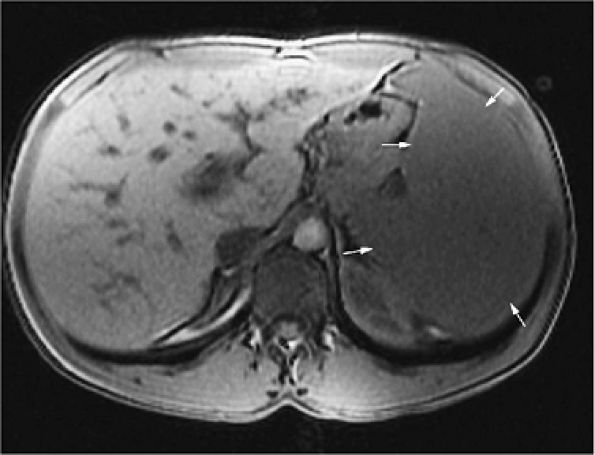

fat fractions correlate with the severity of the disease (Fig. 13.77).118 Displacement of normal marrow fat with Gaucher cells results in bulk T1 increases due to the higher T1 value of water compared with fat.119

FIGURE 13.77 ● Splenomegaly (arrows) is shown on an axial T1-weighted image in a patient with Gaucher disease.